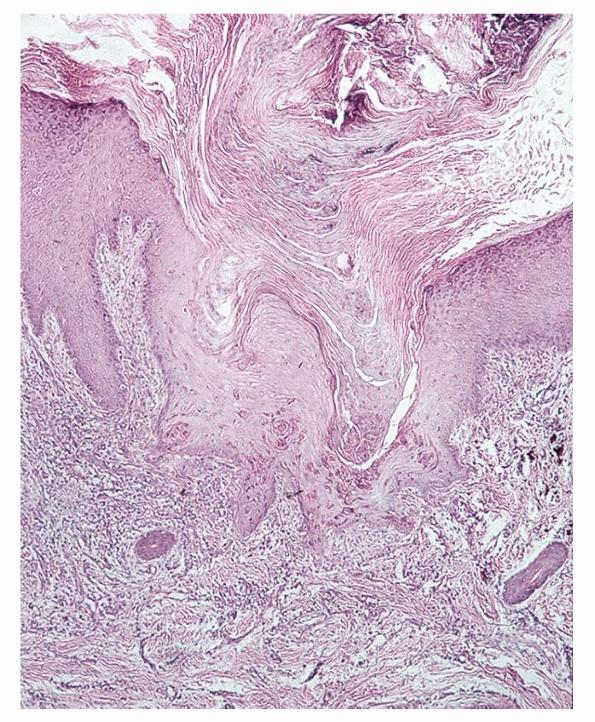

The essential histopathologic findings include (a) a follicular or extrafollicular cornified plug with focal parakeratosis embedded in an epidermal invagination, (b) basophilic degenerated material identified in small collections throughout the plug with absence of demonstrable collagen and elastin, (c) abnormal vacuolated

and/or dyskeratotic keratinization of the epithelial cells extending to the basal cell zone, (d) irregular epithelial hyperplasia, and (e) an inflammatory component that is typically granulomatous with small foci of suppuration (Fig. 15-3). In most instances, it is important to perform elastic tissue stains and even trichrome stains to exclude perforating elastic fibers, as in elastosis perforans serpiginosa, or collagen fibers, as in RPC